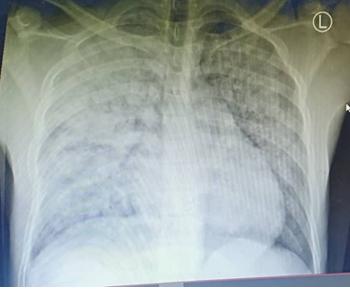

It is my great hope that you are fine wherever you are. This year has been special due to the ongoing COVID 19 pandemic which continues to hit countries all over the world. Amid this pandemic, we had a case which was of a 25 years old man, a Tanzanite miner who has been working for the past three years using only cloth mask for protection from dust. He presented with history of sudden onset of difficulty in breathing following an incident of accidentally touching electrical wires with a bare hand (thumb, index and middle fingers got contact) while climbing out of the mine pit three days prior to admission. The difficulty in breathing was associated with a productive cough which was blood stained and minimal in amount. The patient denied history of being thrown after electrocution or losing consciousness or convulsing or developing fever before or after the incident. Upon arrival at the ED, the primary survey was remarkable for dyspnoea and bilateral coarse crepitations more on the right side. His initial vital signs were BP-133/54 mmHg, PR- 92 beats/min, RR- 24 cycles/min, SPO2- 86% in RA to 98% 10 litres using simple facemask, Temp -36.2*C. The rest of the secondary survey was unremarkable. A diagnosis of low voltage electrical lung injury was suspected. Also since it is COVID 19 era, the patient was treated as a COVID 19 suspect due to the presenting features of DIB and desaturation. A differential of acute silicosis was sought and confirmed by the Chest CT scan later. He was isolated and the nasopharyngeal swab test for COVID 19 was taken. Initial blood works revealed neutrophilia of 86% other parameters were normal, ESR- normal, Electrolytes were normal, Creatinine Kinase was elevated (11.4 U/L), serum creatinine was normal and serology for HIV was negative. Other investigations were ECG which showed sinus rhythm and POCUS showed diffuse B-lines more on right side, normal cardiac contractility.

Figure 1: Chest X-ray which showed bilateral heterogenous opacification more on right side